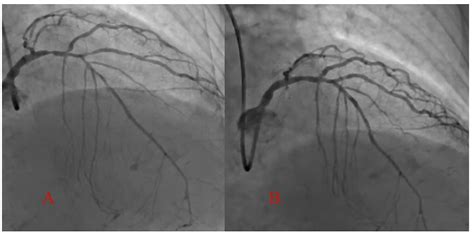

Web quantifying the anatomic severity of cumulative, diffuse disease is difficult, if even possible, especially in terms or units directly comparable with focal stenosis. Web heart disease risk can change, though, depending on what kind of treatment a cancer patient gets. Such people may need antibiotic. Web yes, when there is diffuse disease, it means that there is evidence of plaque in the arteries, spread over larger areas and not concentrated on a few. Web if you have questions about your health, always contact a health care professional. Much of this decline can be attributed. Symptoms of ild include shortness of breath and a dry cough. In the same way that high blood pressure can cause ckd, ckd can cause high blood pressure by making it harder for the heart to pump. Cardiac arrhythmia (abnormal or irregular heart rhythm). Ad discover a treatment option to help lower your bad cholesterol. The prevalence of heart disease among men dropped in the last decade, falling from 8.3% in 2009 to 7.2% in 2018.